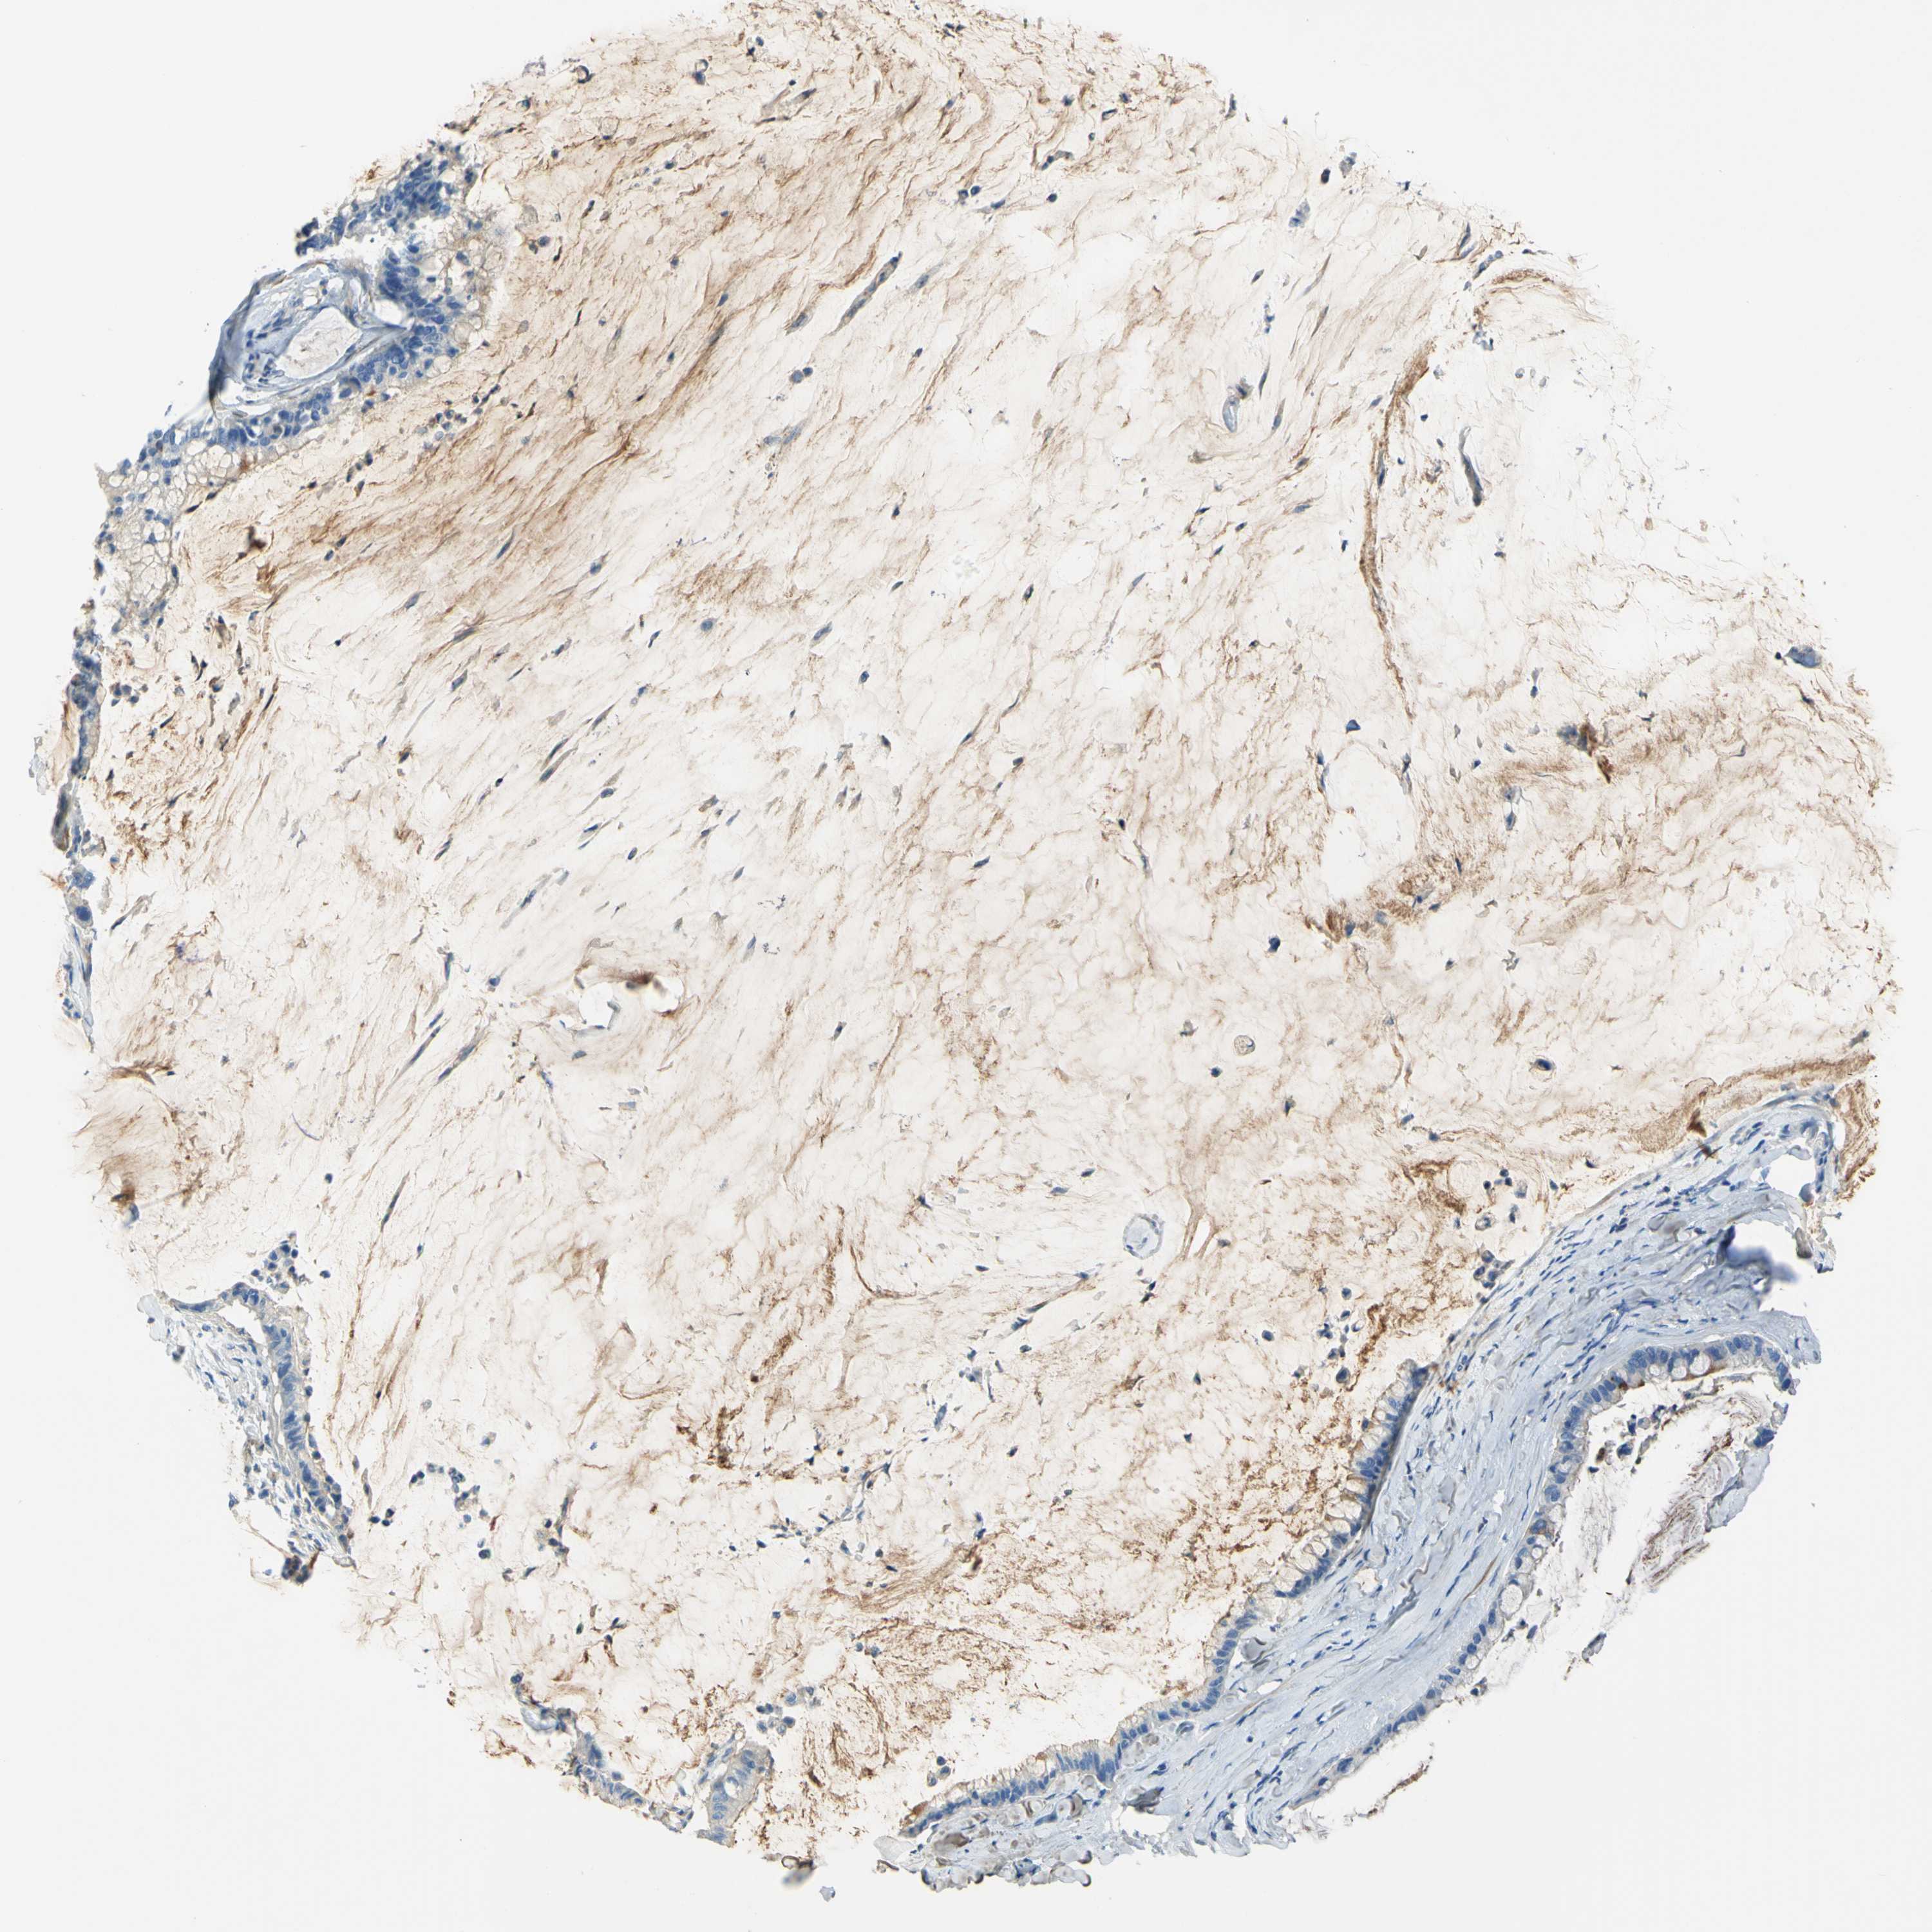

PANCREATIC CANCER - Protein expressioni

A mouse-over function shows sample information and annotation data. Click on an image to view it in a full screen mode. Samples can be filtered based on level of antibody staining by selecting one or several of the following categories: high, medium, low and not detected. The assay and annotation is described here.

Note that samples used for immunohistochemistry by the Human Protein Atlas do not correspond to samples in the TCGA dataset.

Antibody stainingi

Antibody staining in the annotated cell types in the current human tissue is reported as not detected, low, medium, or high, based on conventional immunohistochemistry profiling in selected tissues. This score is based on the combination of the staining intensity and fraction of stained cells.

Each image is clickable and will lead to virtual microscopy that enables deeper exploration of all samples and also displays staining intensity scores, fraction scores and subcellular localization as well as patient and tissue information for each sample.

Antibody HPA013132

Staining

High

Medium

Low

Not detected

Intensity

Strong

Moderate

Weak

Negative

Quantity

>75%

75%-25%

<25%

None

Location

Nuclear

Cytoplasmic/membranous

Cytoplasmic/membranous,nuclear

Adenocarcinoma, NOS